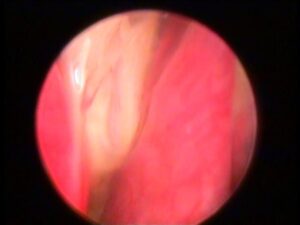

Nelle foto un tappo di birra, rimasto per 10 gg nello stomaco di un cucciolo di 4 mesi, come visualizzato alla radiografia e, successivamente in gastroscopia, procedura che ne ha permesso l’asportazione in modalità non invasiva.

Asportazione corpo estraneo tramite endoscopia esofagea

Capita con una certa frequenza che giocando i cani deglutiscani materiali che non riuscendo a raggiungere lo stomaco rimangono letteralmente incastrati nell’esofago.

Si parla quindi id corpi estranei esofagei.

I sintomi sono immediati (perdita di saliva, tentativi di deglutizione continui, rigurgito, irrequietezza.

La maggior parte delle volte è possibile rimuoverli in modo non invasivo, tramite esofagoscopia, in anestesia generale, tramite videoendoscopia, con apposita pinza da presa.